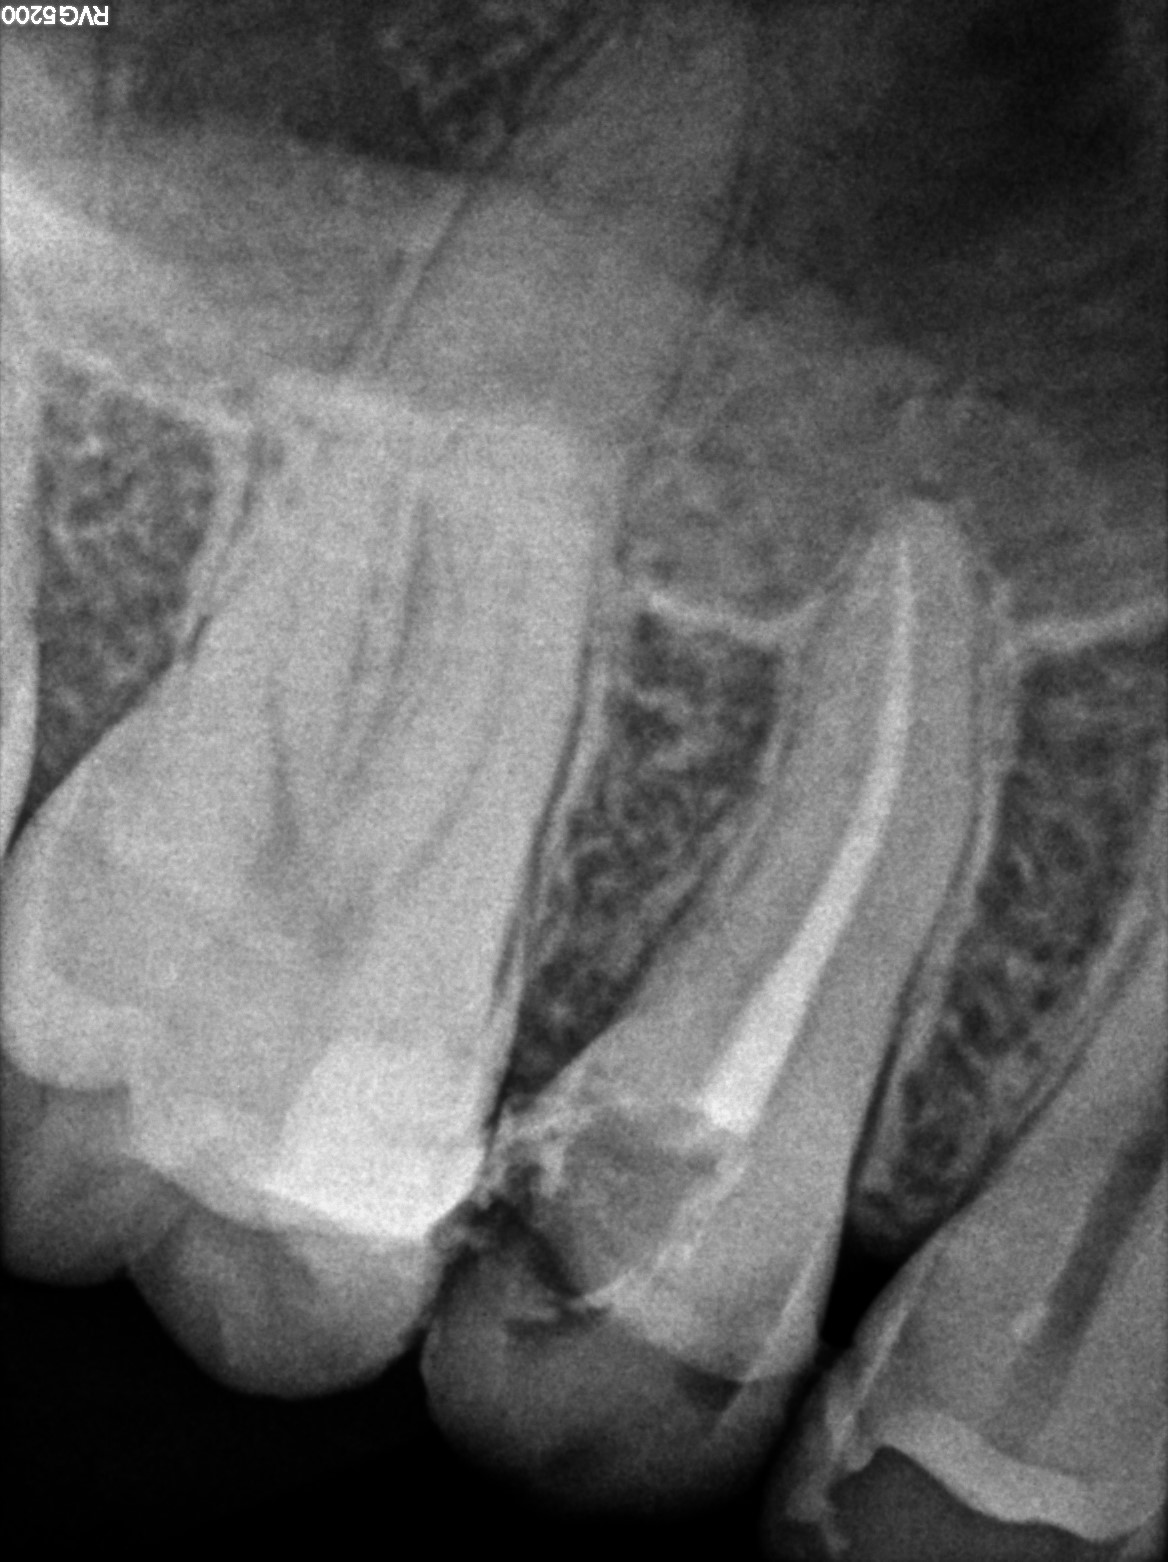

Dental Radiographs FHIR: DocumentReference · LOINC 24641-7

R55.jpg

24641-7